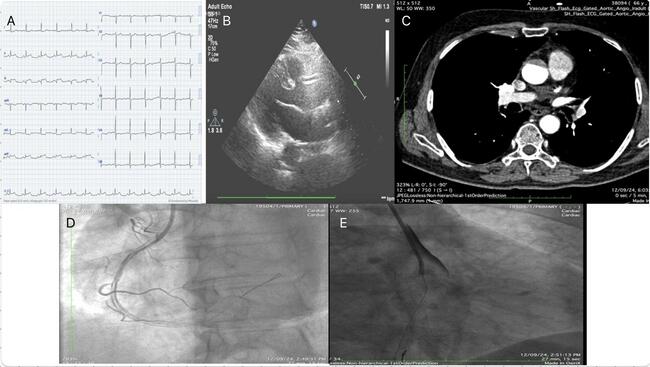

A 52-year-old man presented to the emergency department with chest pain and diaphoresis for the past 4 hours. The pain was maximum at onset, retrosternal, and radiating to his back. Upon admission, he was afebrile with a pulse rate of 70 beats per minute, respiratory rate of 20 breaths per minute, and blood pressure of 210/110 mm Hg. The patient had no prior history of hypertension, diabetes, or smoking. A 12-lead electrocardiogram (ECG) showed ST-segment elevation in the inferior leads with reciprocal changes in leads I and aVL, indicating an acute inferior wall myocardial infarction (Figure A). Screening transthoracic echocardiography was suggestive of inferior basal wall hypokinesia with an ejection fraction of 50%. The patient was taken for urgent coronary angiography, which revealed mild plaquing in the proximal left anterior descending artery and a 100% thrombotic cutoff of the ostia-proximal right coronary artery (RCA).

Given the diagnosis, the decision was made to proceed with angioplasty of the RCA. The RCA was successfully wired with a workhorse wire, and balloon inflation was performed at the site of the lesion. However, following balloon inflation, a spiral dissection of the artery was noted (Figure D). In response, an aortic angiogram was performed, which revealed a Type A aortic dissection (Figure E) and lead to the abandonment of the procedure.

Retrospectively, on a closer look at the echocardiogram, an intimal flap in the ascending aorta with acute aortic regurgitation was seen (Figure B). A computed tomography scan subsequently confirmed the presence of aortic dissection (Figure C), and the patient was immediately referred to cardiothoracic and vascular surgery where he underwent the Wheat procedure (aortic valve replacement with supra-coronary ascending aorta replacement) along with grafts to the RCA. He was subsequently discharged.